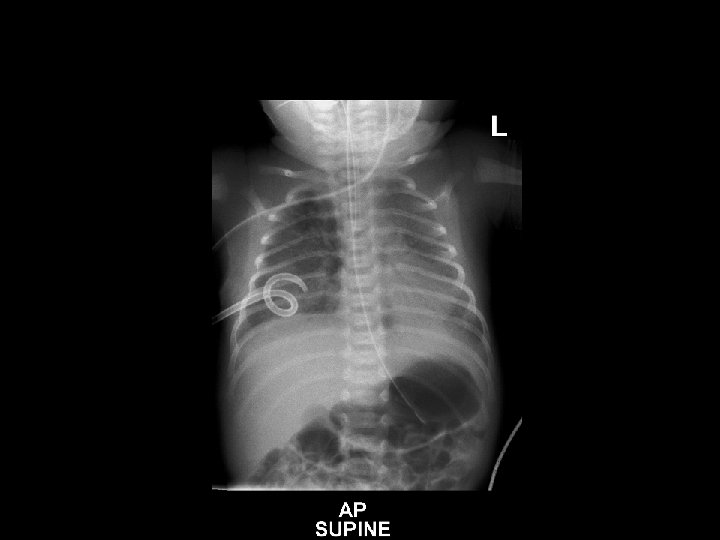

6. XRAY interpretation (31/8/12 @ 1643 hrs) • Bilateral but diffuse reticular granular densities • Lungs do not appear hyperinflated • No pleural effusions • Heart is not enlarged • NG tube is noted, tip below L) hemidiaphragm Impression: findings would favour hilar membrane disease (RDS), with infection also in the differential